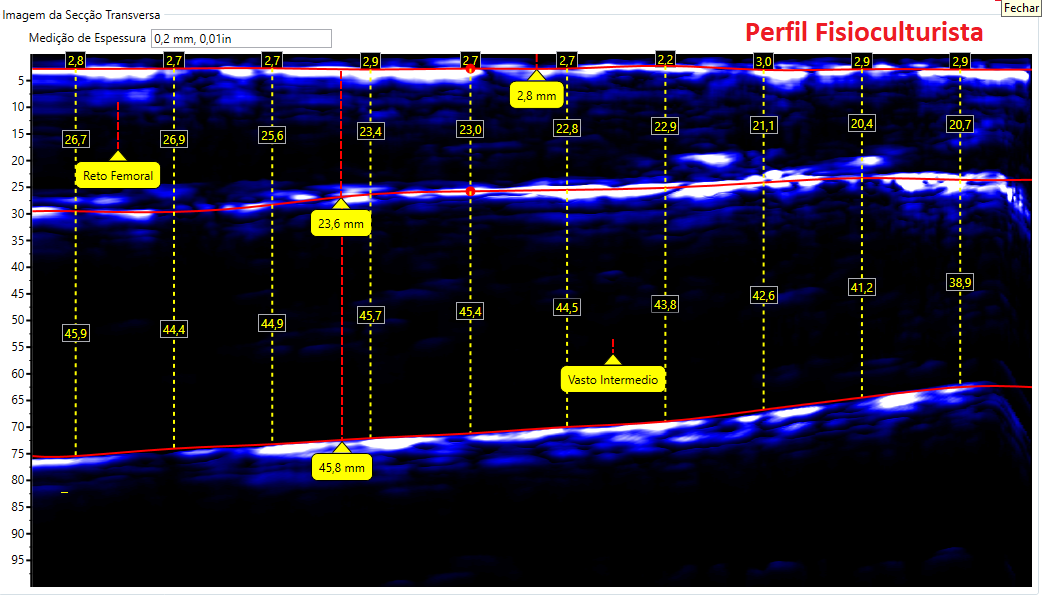

Comparativos de imagens de Coxa